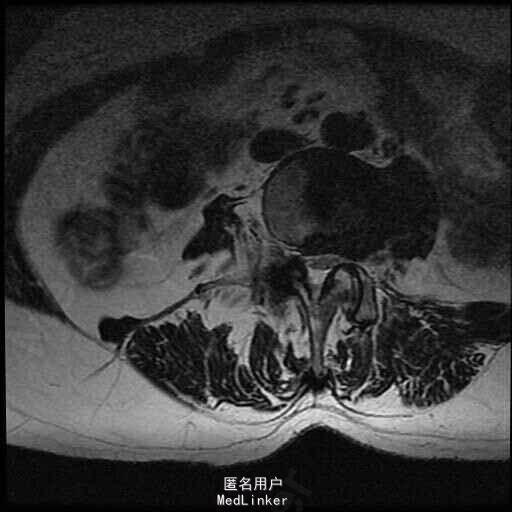

查体:脊柱侧弯,上肢无麻木,疼痛感觉异常,腰部右侧疼痛,右下肢及右臀部疼痛,麻木感。双侧肌力及肌张力可,膝腱反射(+),踝反射(+),病理征(—),直腿抬高试验。右侧40度,左侧55度。 辅助检查:腰椎x线片:腰椎侧弯,腰椎退行性改变,L5椎体略行前滑脱 脊柱全长:胸腰段呈S形,L5椎体向前滑脱,L3椎体略变扁,颈胸腰椎退行性改变 MRI:脊柱侧弯,L2-3,L3-L4,L4-L5,L5-S1椎间盘突出,相应节段椎管狭窄

诊断:腰椎侧弯,腰椎椎管狭窄 治疗:手术矫形:早期侧路减压融合,后期再行后路固定。